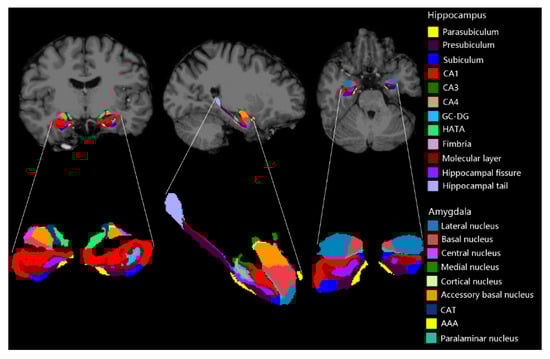

2.2. Imaging Processing

- Iglesias, J.E.; Augustinack, J.C.; Nguyen, K.; Player, C.M.; Player, A.; Wright, M.; Roy, N.; Frosch, M.P.; McKee, A.C.; Wald, L.L.; et al. A computational atlas of the hippocampal formation using ex vivo, ultra-high resolution MRI: Application to adaptive segmentation of in vivo MRI. NeuroImage 2015, 115, 117–137. [Google Scholar] [CrossRef]

- Saygin, Z.; Kliemann, D.; Iglesias, J.E.; Van Der Kouwe, A.; Boyd, E.; Reuter, M.; Stevens, A.; Van Leemput, K.; McKee, A.; Frosch, M.; et al. High-resolution magnetic resonance imaging reveals nuclei of the human amygdala: Manual segmentation to automatic atlas. NeuroImage 2017, 155, 370–382. [Google Scholar] [CrossRef]